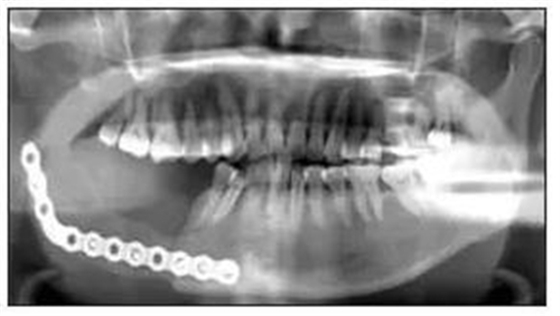

免疫組織化學(xué)結(jié)果:S100彌漫陽性、CD21陰性、CD57陰性、CR陽性、結(jié)蛋白陰性、鈣調(diào)結(jié)蛋白陰性、ALK陰性、PCK陰性、Ki-67表達(dá)2%~5%陽性(圖2)。1.5 隨訪患者術(shù)后切口愈合良好,牙無松動,咬合關(guān)系良好。術(shù)后復(fù)查顯示傷口愈合良好,骨斷端生長良好(圖3)。

圖3 術(shù)后全景片